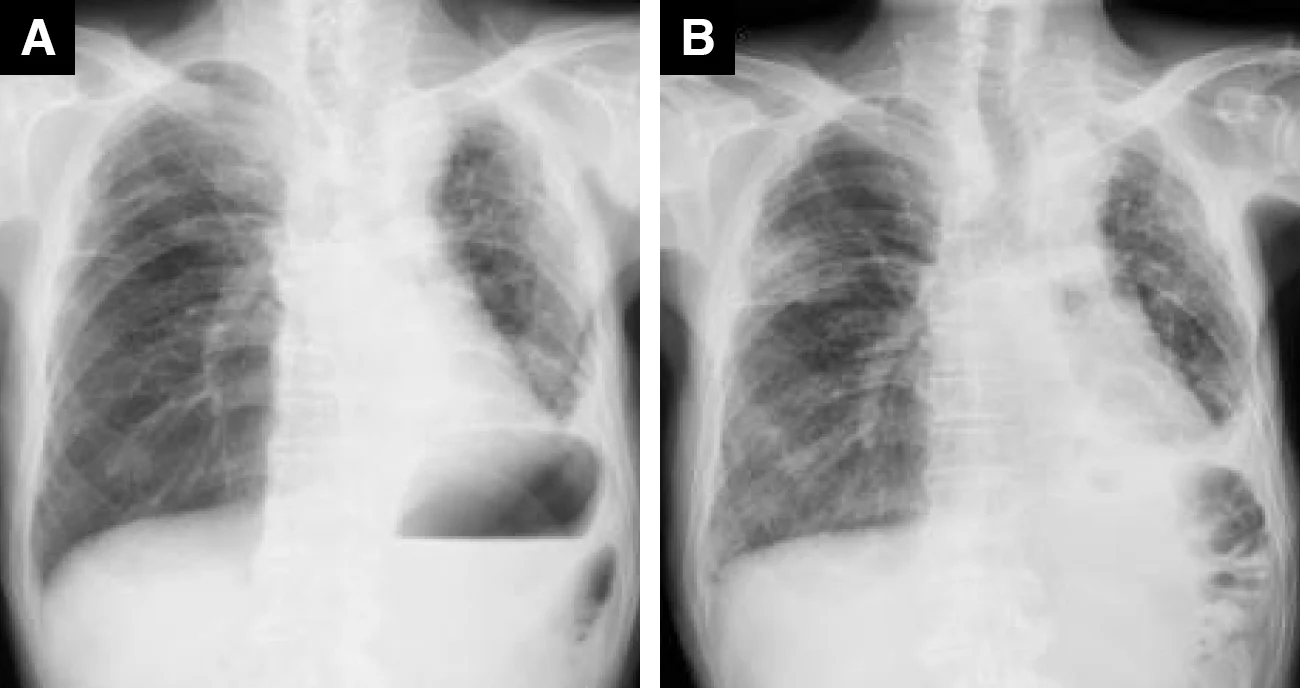

ゲフィチニブ投与症例(82歳、男性、肺腺がん)

A : 薬剤投与前 B : 薬剤投与後(紹介時)

Bでは広範囲のすりガラス影~微細粒状影の出現を認めた

A、B : 薬剤投与後(紹介時)

非区域性に広がるすりガラス影のなかに牽引性気管支拡張所見がみられ、DAD(びまん性肺胞障害)パターンを呈していた